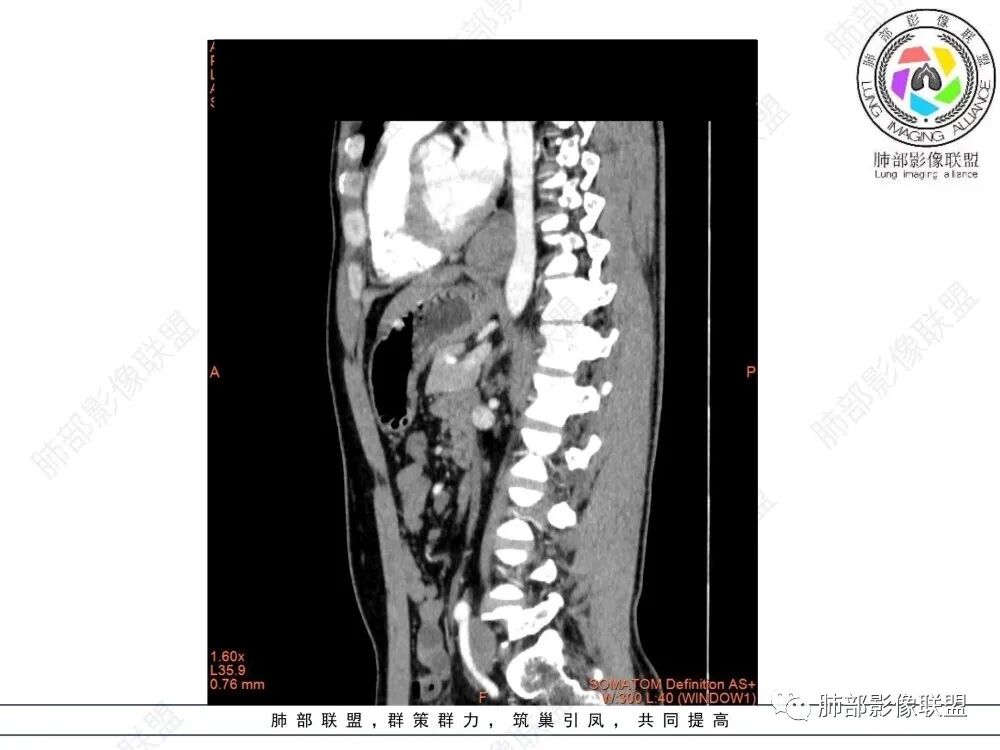

影像学特点:类纵隔区病变,沿食管生长,形态不规则,但边界清楚,内部信号/密度均匀,强化程度比较弱。

影像诊断思路:起源食管肿瘤(非黏膜起源,肌层起源),良性或低度恶性肿瘤可能性大,一般以神经鞘瘤、胃肠间质瘤及平滑肌瘤为主。食管神经鞘瘤强化明显均匀、以食管上段多见,周围常见炎性增大淋巴结,不太符合;胃肠间质瘤小的比较均匀,大的不均匀,但强化程度较高;影像上看这例病例比较符合平滑肌瘤。

食管平滑肌瘤是最常见的食管良性肿瘤,多见于男性,男女之比为2.6:1,高发年龄 30~60岁之间与食管癌相比,食管平滑肌瘤 的一个主要特点是病史相对较长,病情进展缓慢。病史最长者达10年余,平均 15.7个月,尽管病史较长,但大多数患者仍能进普食。食管平滑肌瘤的诊断一般比较容易,结合患者临床症状、食管造影及食管镜所见,一般均能得出正确诊断。食管造影主要为充盈缺损,病变与食管壁成锐角,粘膜线连续无破坏,管腔收缩扩张比较自如。钡餐造影敏感性高,但对食管壁间及食管周围情况难以判断。CT具有极高的密度分辨率,并且可以获得高质量的多平面重组图像,有利于食管壁间及食管周围情况的判断,表现为食管下段环绕管壁生长,偏心性或薄厚不均软组织密度肿块,密度均匀,内缘分叶状,管腔与正常食管壁构成不规则多角形扩张,增强动脉期无强化,多角度重建其病灶长轴与食管长轴不一致。由于食管壁在收缩状态下厚度约为5.6mm,扩张状态厚度不超过3mm,CT扫描时保持食管处于扩张状态可提高小病灶检出率。MR表现为T1加权等信号,T2加权稍高信号,可见高信号粘膜层,增强扫描轻度渐进性强化,密度均匀,无出血坏死。对于粘膜及周围脂肪间隙的判断具有明显优势。